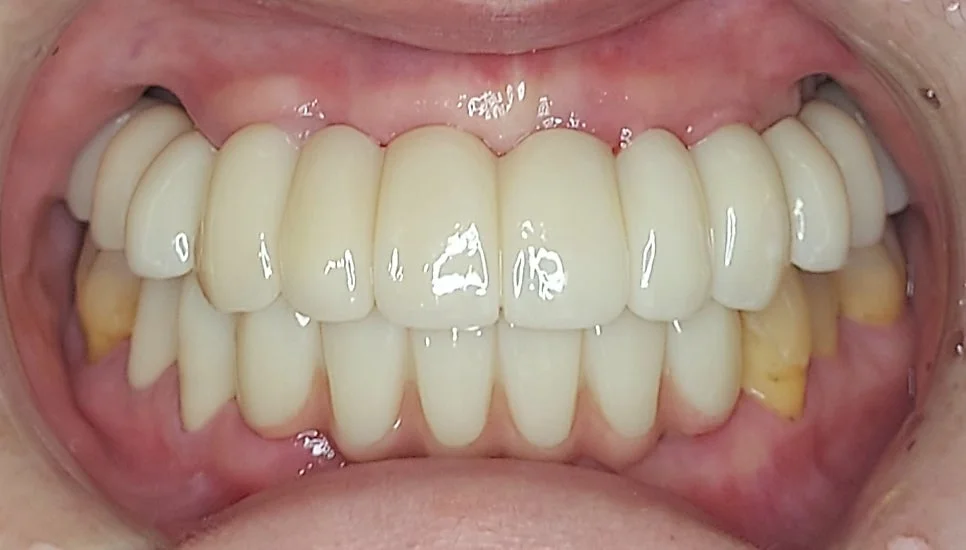

보철 과정 – Before / 임시 / 최종 완성

대략 2~4개월 정도의 임플란트 유착 기간 후에 보철물 제작에 들어가게 됩니다. 임시 치아를 상당 기간 사용한 후 최종 보철물을 제작합니다.

남아 있는 잇몸을 기준으로 치아의 높이를 결정하고, 위아래 입술의 위치에 따라 전후방 위치를 결정하고, 웃는 모습을 기준으로 치아를 이상적으로 배열하고, 최대한 자연스러운 색상으로 환자분과 결정합니다.